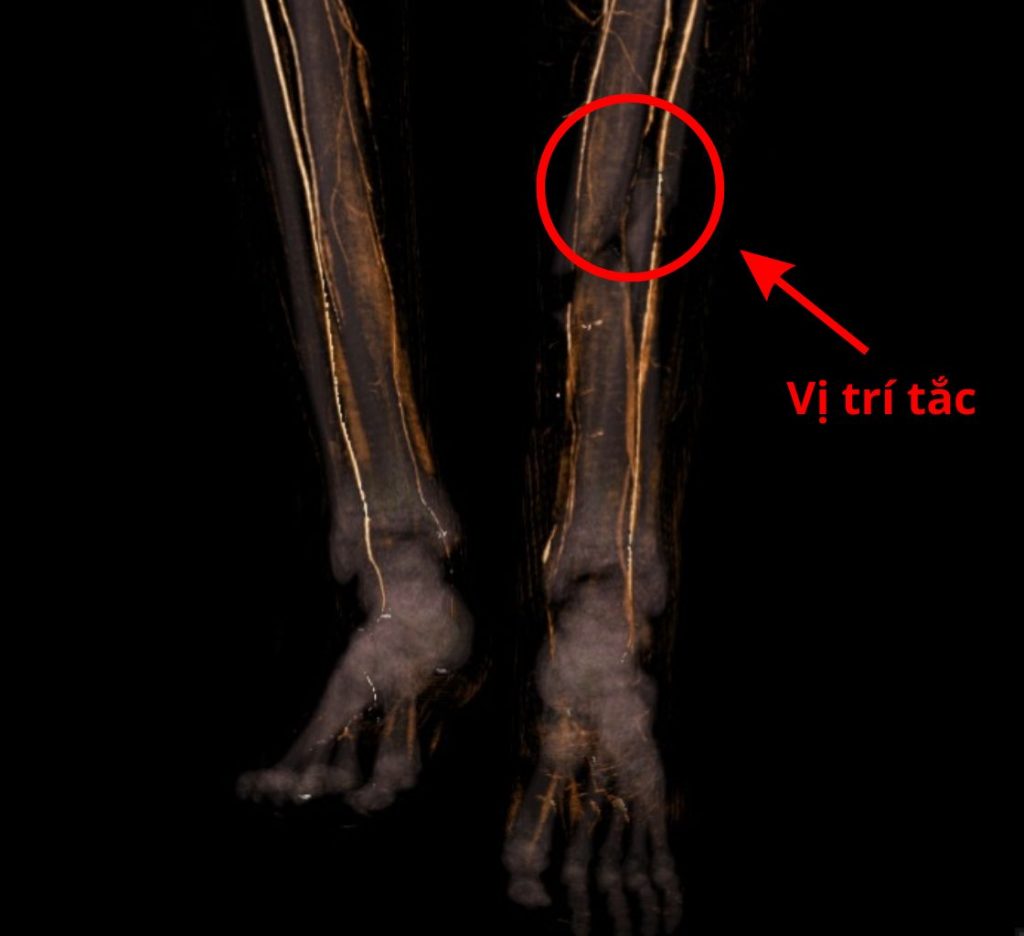

Hình ảnh CT mạch máu

Khoảng 30 phút trước khi nhập viện, em N.C.L (19 tuổi, ngụ Tây Ninh) đang điều khiển xe máy thì xảy ra va chạm với xe tải. Khi được đưa đến Bệnh viện Đa khoa Xuyên Á Đức Hòa, em trong tình trạng: gãy hở độ cẳng chân trái, gãy đầu dưới xương mác trái, cẳng chân tím tái, bàn chân sưng nề, đầu ngón kém hồng hào, mạch mu chân và mạch chày sau gần như không bắt được, dấu hiệu cho thấy chi thể đang rơi vào tình trạng thiếu máu cấp.